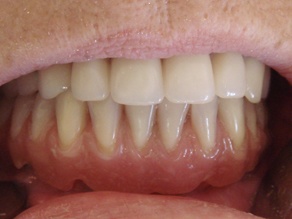

La prothèse est vissée en bouche

Cas terminé avec la prothèse maxillaire.